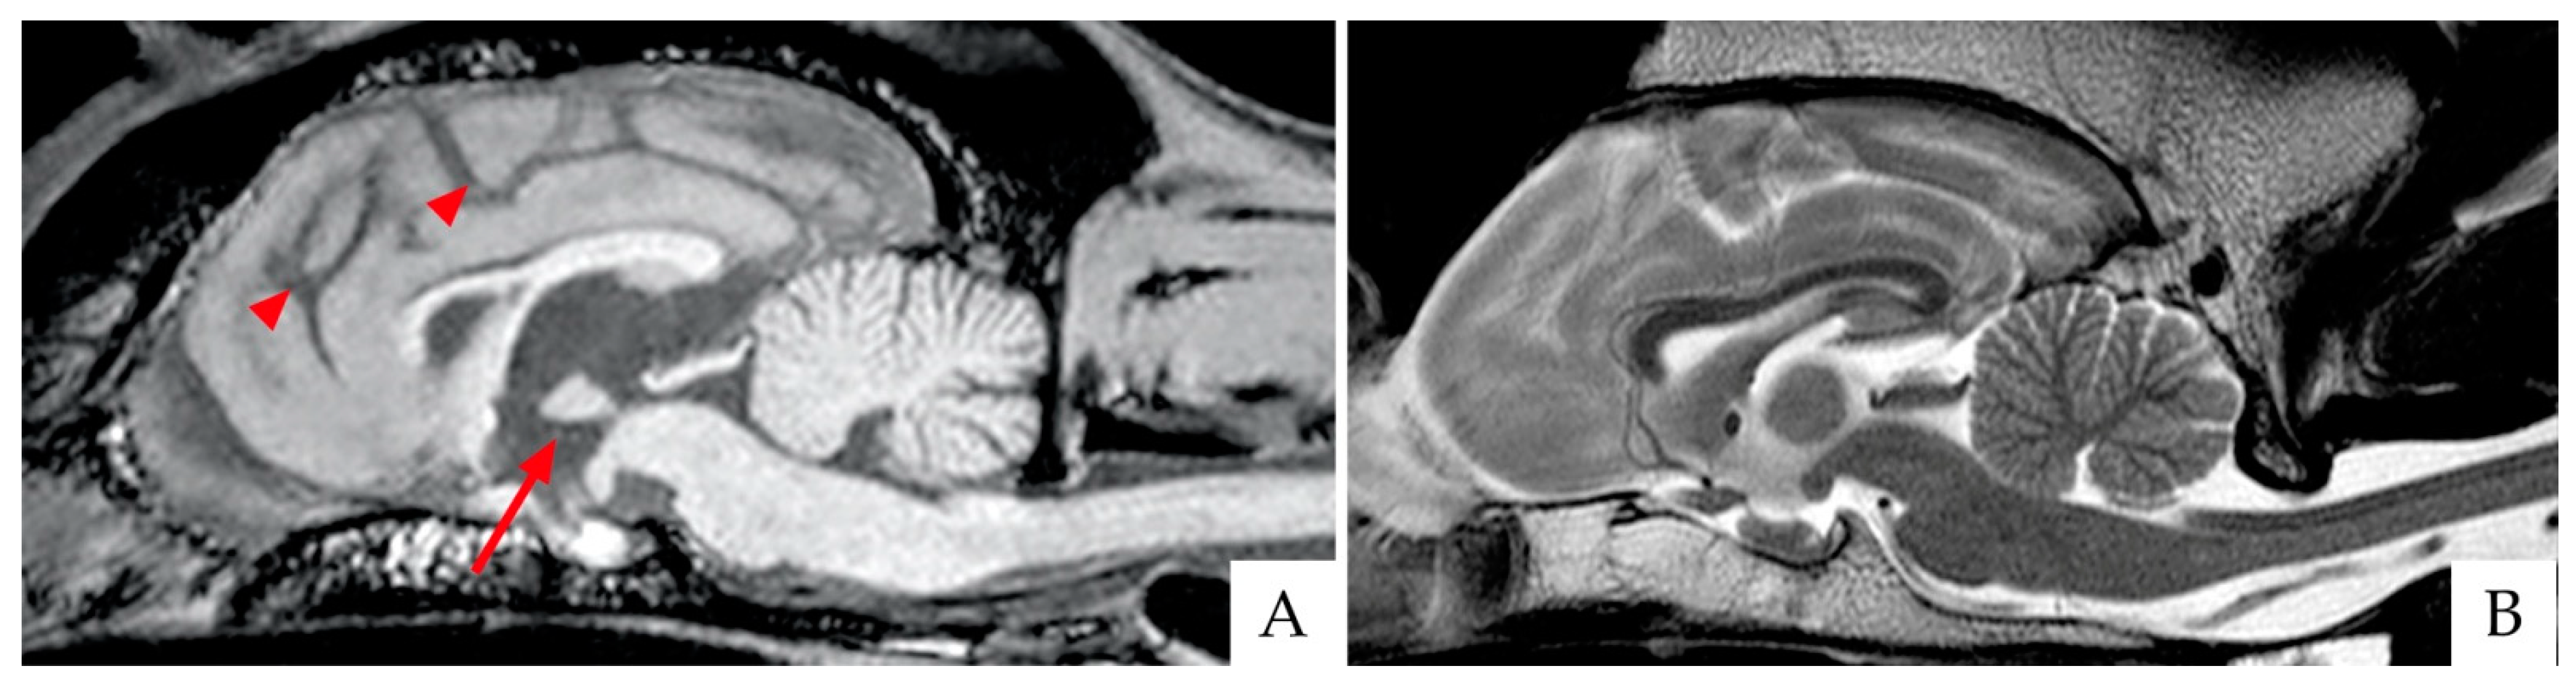

Although in veterinary medicine evidence, imaging research is scanty compared to the human field, magnetic resonance imaging (MRI) has been recently applied not only to rule out other causes (e.g., brain tumors) but also to gain insight into CDS-associated brain changes. Canine normal brain aging is associated with the volumetric reduction of the frontal cortex, basal ganglia, and hippocampus [51], resulting from the progressive loss of white matter and the subsequent expansion of the ventricular system [52,53]. MRI studies have highlighted that brains from “successfully aging” dogs exhibit less generalized brain atrophy, while brains from CDS animals show more severe and progressive forebrain atrophy paralleling the degree of cognitive impairment [54]. More recently, MRI investigations in dogs confirmed that forebrain atrophy is mainly due to white matter reduction [55,56], decreased hippocampal volume [57], and reduced interthalamic adhesion [58,59] (Figure 2). In particular, an interthalamic adhesion size of 3.82 ± 0.79 mm has been associated with CDS [58]. Increased microhemorrhages [59] and higher signal intensity of the white matter or leukoaraiosis [60] have also been reported in brains from pets affected by CDS.

Figure 2.

Brain scans of two breed-matched old dogs affected (A) and unaffected (B) by CDS, as acquired with 3 Tesla magnetic resonance imaging (3T MRI). (A) Sagittal T1 weighted image (T1WI). Please note the reduced size of the interthalamic adhesion (arrow) and the increased sulci (arrowheads). (B) Sagittal T2WI of the normal control dog.